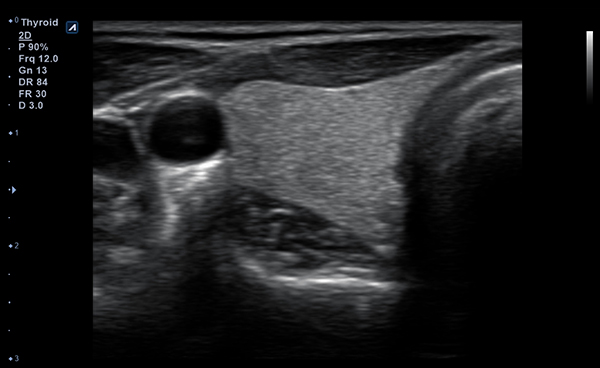

Alpinion Medical Systems, la empresa de sistemas de ultrasonido, ha combinado tecnologías

de procesamiento de imágenes y transductores para garantizar que minisono proporcione

imágenes 2D de alta definición e información de Doppler más claras y nítidas.

minisono ofrece funciones esenciales con el nivel de rendimiento necesario

para garantizar que los exámenes y diagnósticos sean precisos.

- Frequency3-12 MHz

- Dimension (height/width/depth)25.2 / 62.5/ 150mm

- Weight 175g

- Field of view 38.4mm

- Max depth10 cm

- Imaging modesB-mode, CF, M, PW, PD

- DisplayMicrosoft Surface

- Battery300 min